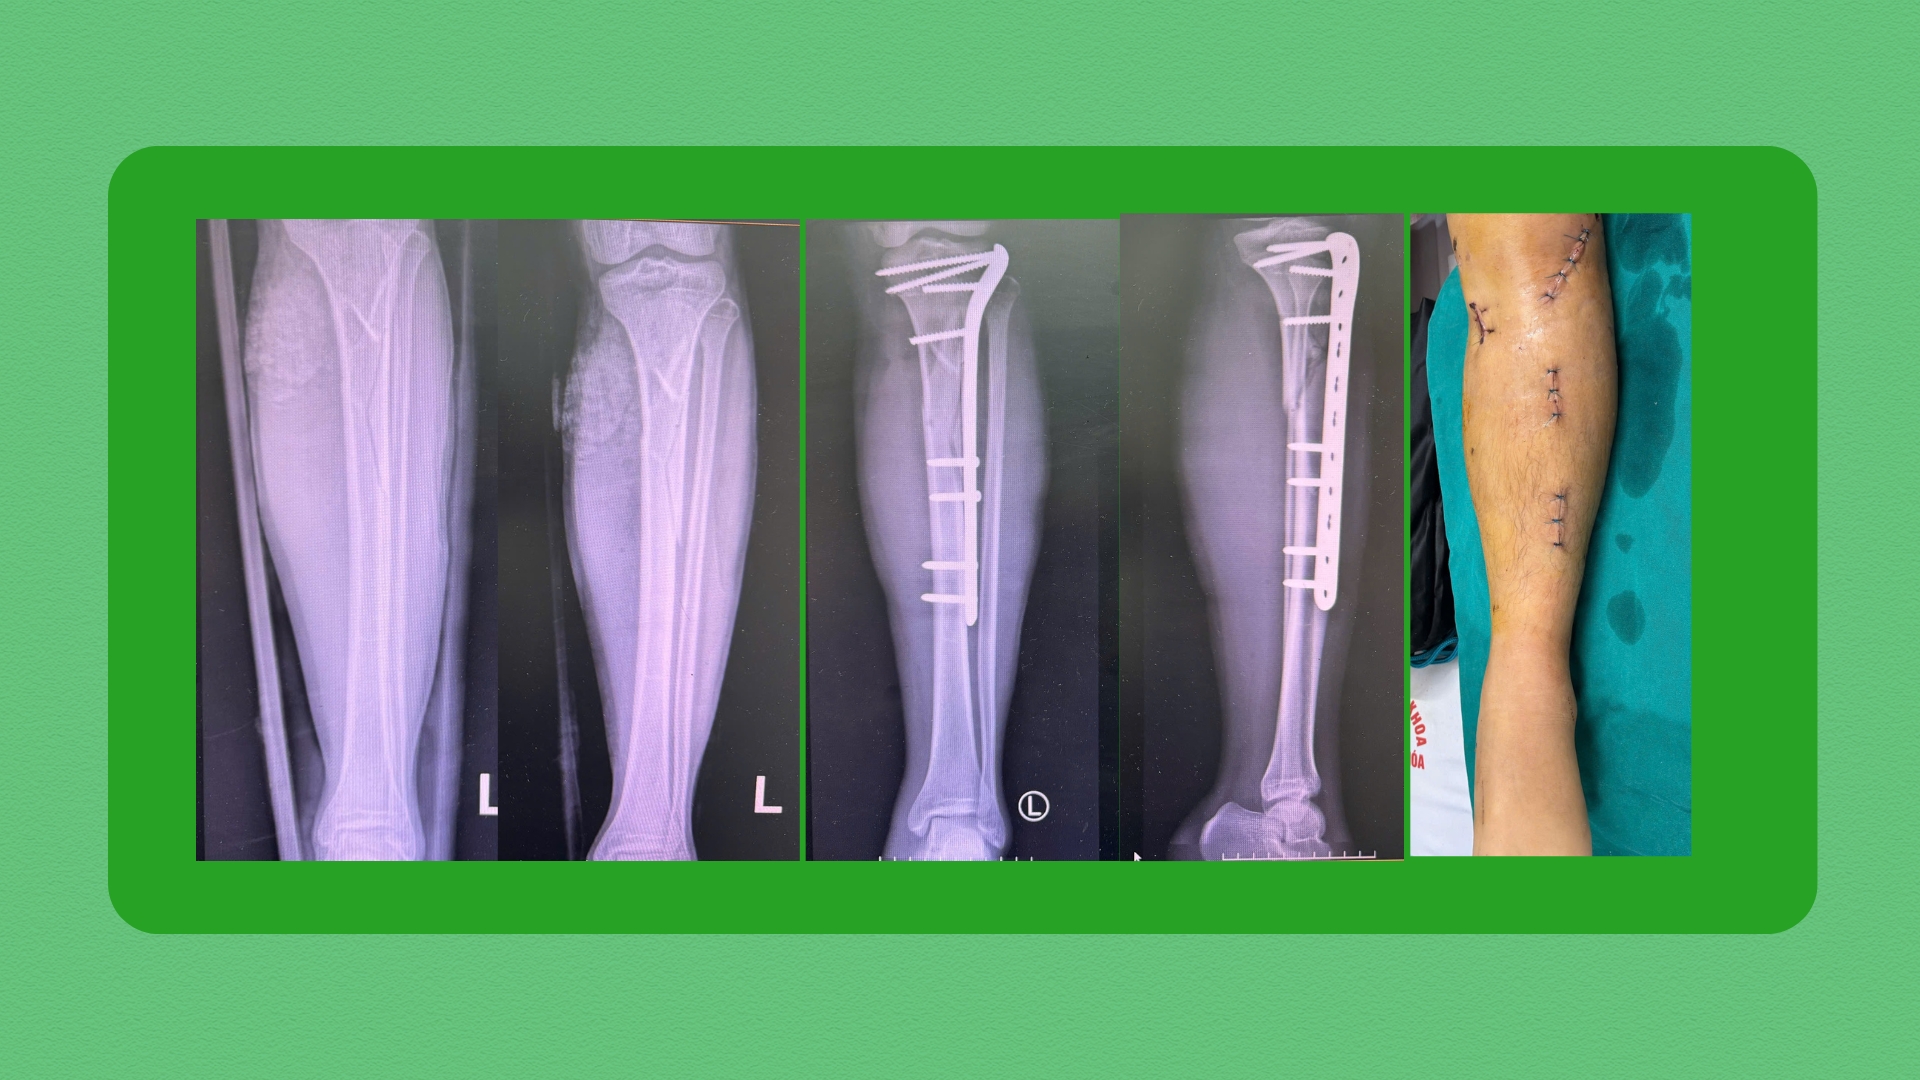

Hình ảnh phim chụp của bệnh nhân T. trước và sau phẫu thuậtQua thăm khám lâm sàng và xét nghiệm cận lâm sàng, bệnh nhân được chẩn đoán xác định gãy phức tạp đầu trên xương chày trái. Sau hội chẩn, các bác sĩ quyết định thực hiện phương pháp kết hợp xương nẹp vít bằng MIPO, nắn chỉnh kín dưới màn tăng sáng C-arm.

Chỉ sau một ngày phẫu thuật, bệnh nhân đau nhẹ, ít sưng nề, đã được tiến hành tập phục hồi chức năng các bài tập chủ động như gấp duỗi cổ chân, gối và khớp háng. Chia sẻ sau phẫu thuật, bệnh nhân cảm thấy rất hài lòng và tin tưởng phương pháp điều trị.

Một số hình ảnh trước và sau phẫu thuật của bệnh nhân được sử dụng kỹ thuật MIPO trong phẫu thuật kết hợp xương